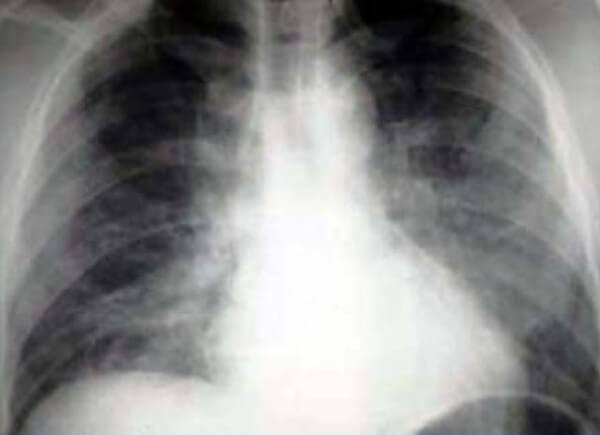

Интерстициальная пневмония на снимке